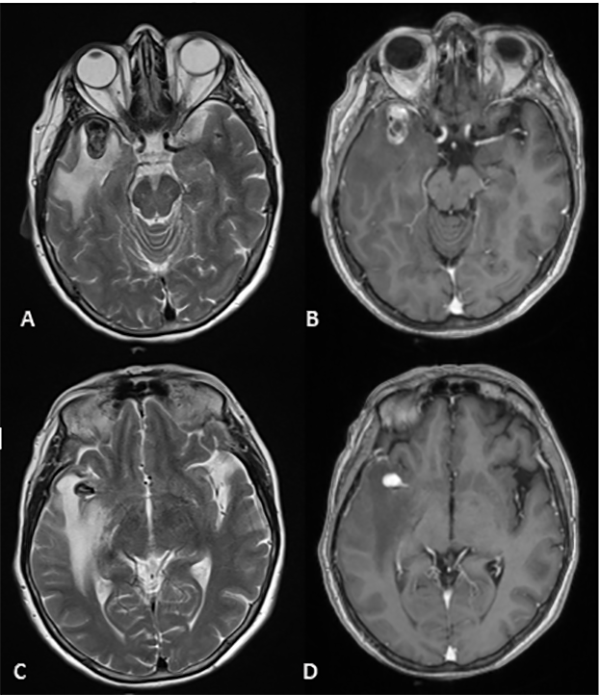

Paciente femenina de 72 años de edad con antecedentes de hipertensión arterial, dislipidemia, sobrepeso y extabaquista, a quien en contexto de estudio por hipoacusia neurosensorial se le realizó RM de cerebro y conductos auditivos internos con contraste endovenoso, en la cual se observó como hallazgo incidental lesión expansiva marcadamente hipointensa en T2 localizada a nivel temporal anterior derecho de aproximadamente 23 x 14 mm de diámetro en relación con el sector distal de la arteria cerebral media homóloga. Tras la inyección de contraste presentó refuerzo heterogéneo, con un componente de aspecto trombosado en el sector basal de la misma, asociado a extenso edema periférico (Figura 3). Se decidió realizar consulta con especialidad de neurocirugía quien sugirió completar la aproximación diagnóstica con AD de vasos intracraneanos en la cual se observó a nivel silviano derecho dilatación aneurismática de contornos lobulados con diámetros de 10.7 x 9.7mm, no presentando un cuello favorable para el acceso endovascular (Figura 4 y 5). En dicho estudio se menciona además pequeño aneurisma de 2mm en arteria comunicante anterior y otro silviano izquierdo de 4mm.

Figura 3: (RMN) Se observa en corte axial lesión expansiva marcadamente hipointensa en T2 localizada a nivel temporal anterior derecho en relación con el sector distal de la arteria cerebral media homóloga. Tras la inyección de contraste presentó refuerzo heterogéneo, con un componente de aspecto trombosado en el sector basal de la misma, asociado a extenso edema periférico (A, B, C y D).